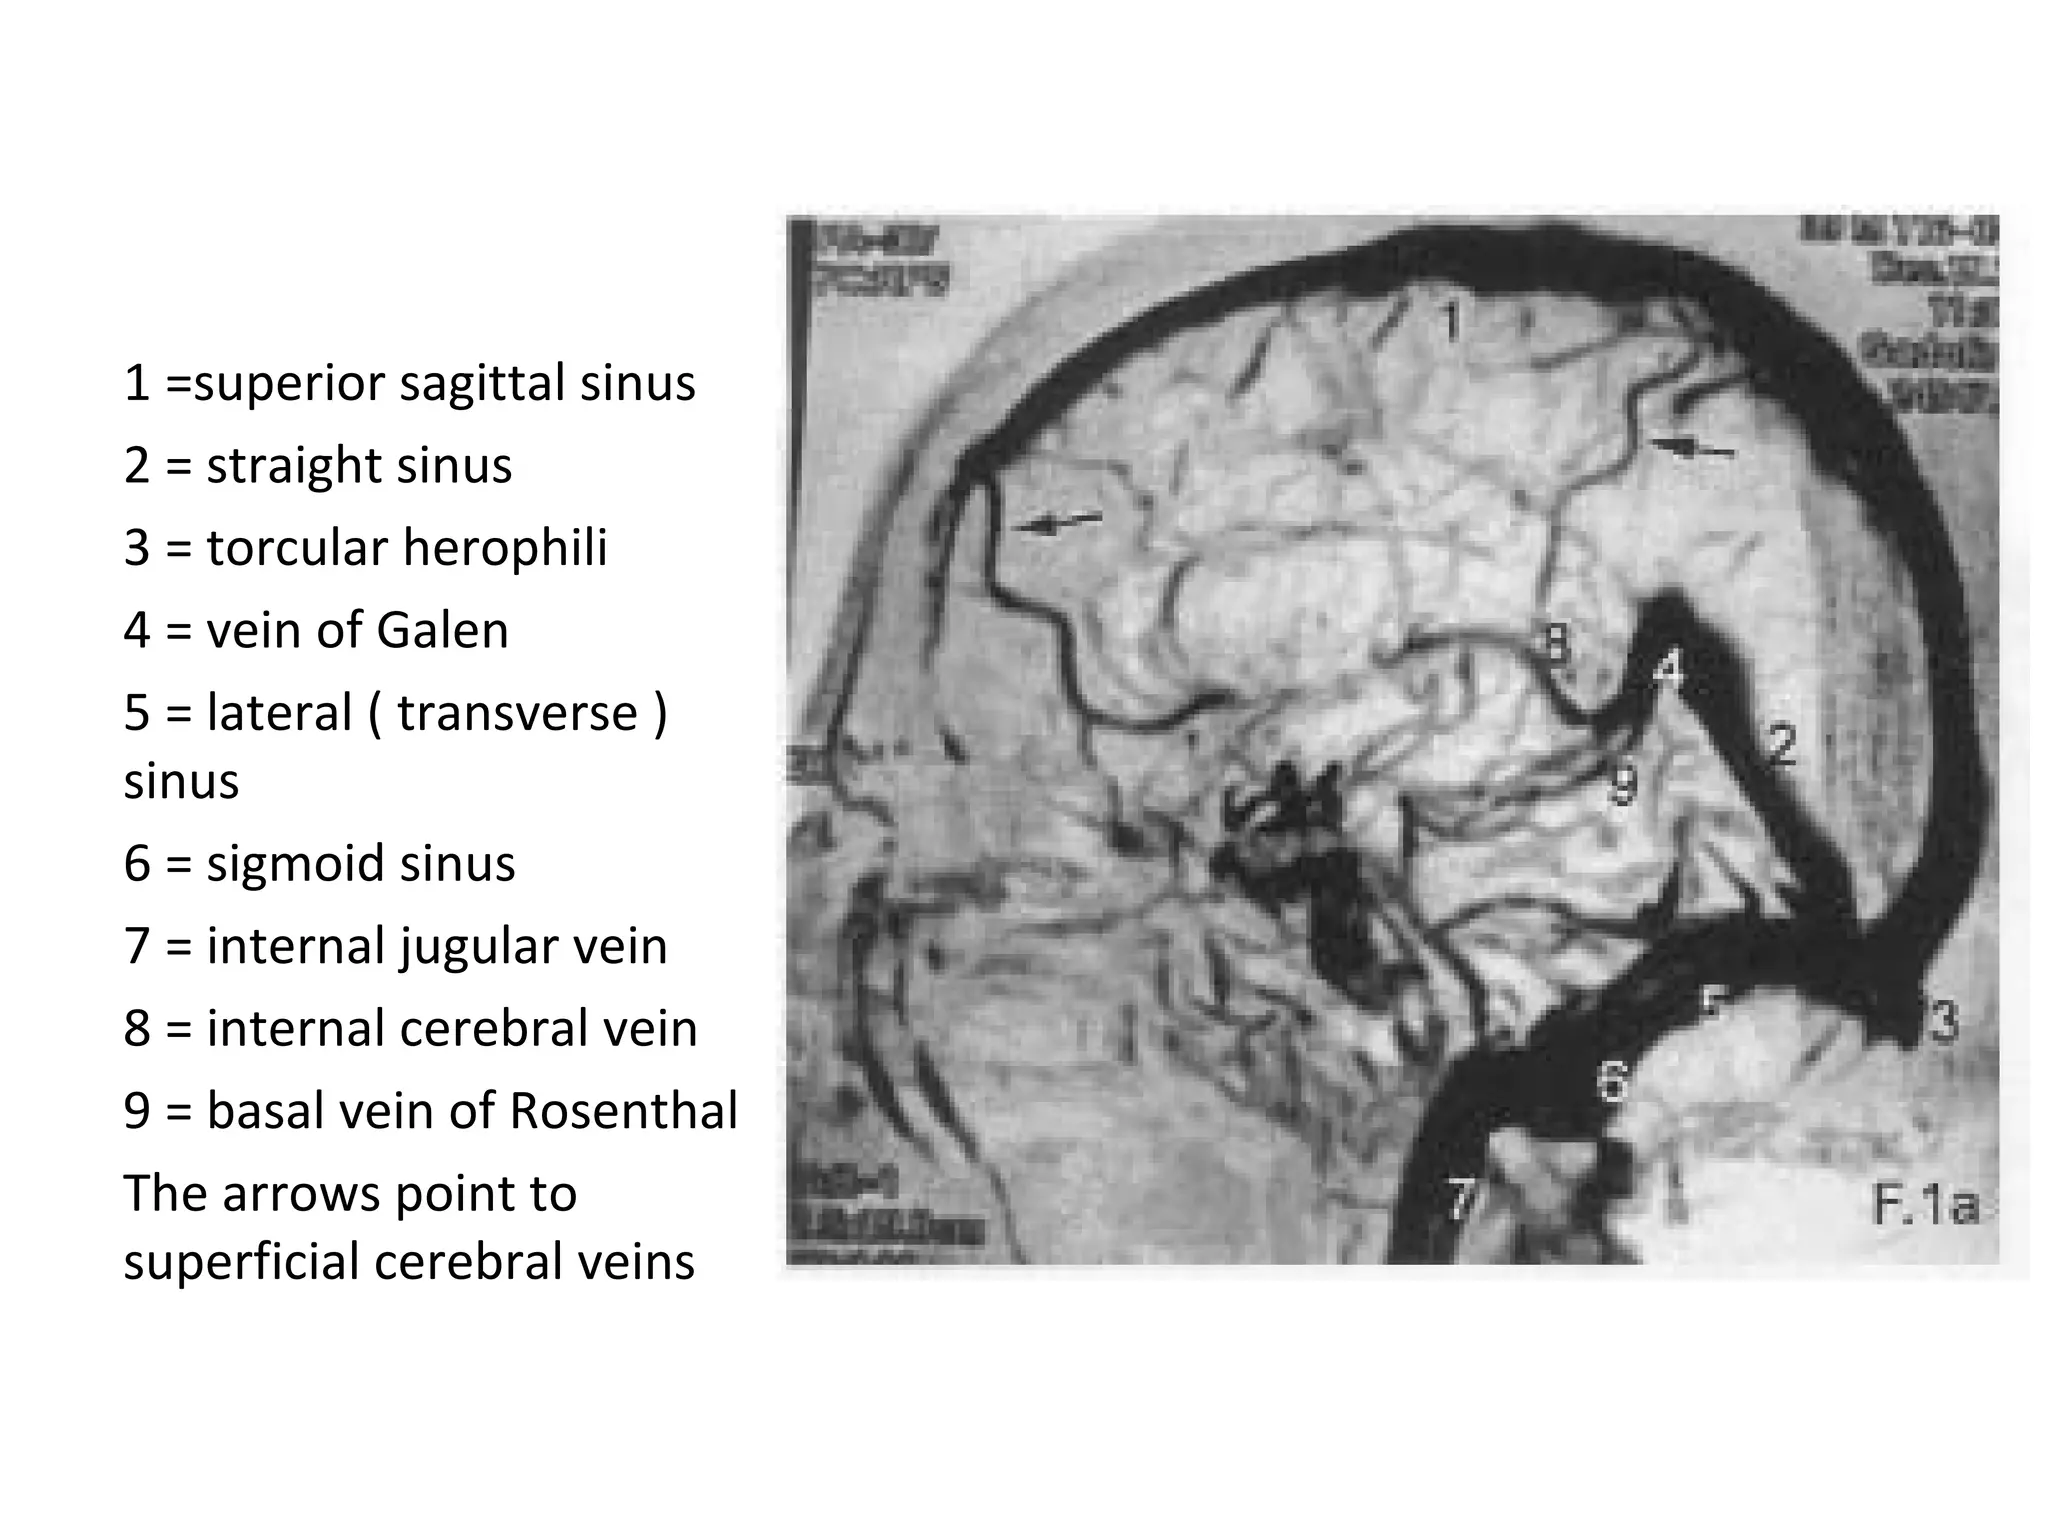

1 =superior sagittal sinus

2 = straight sinus

3 = torcular herophili

4 = vein of Galen

5 = lateral ( transverse )

sinus

6 = sigmoid sinus

7 = internal jugular vein

8 = internal cerebral vein

9 = basal vein of Rosenthal

The arrows point to

superficial cerebral veins